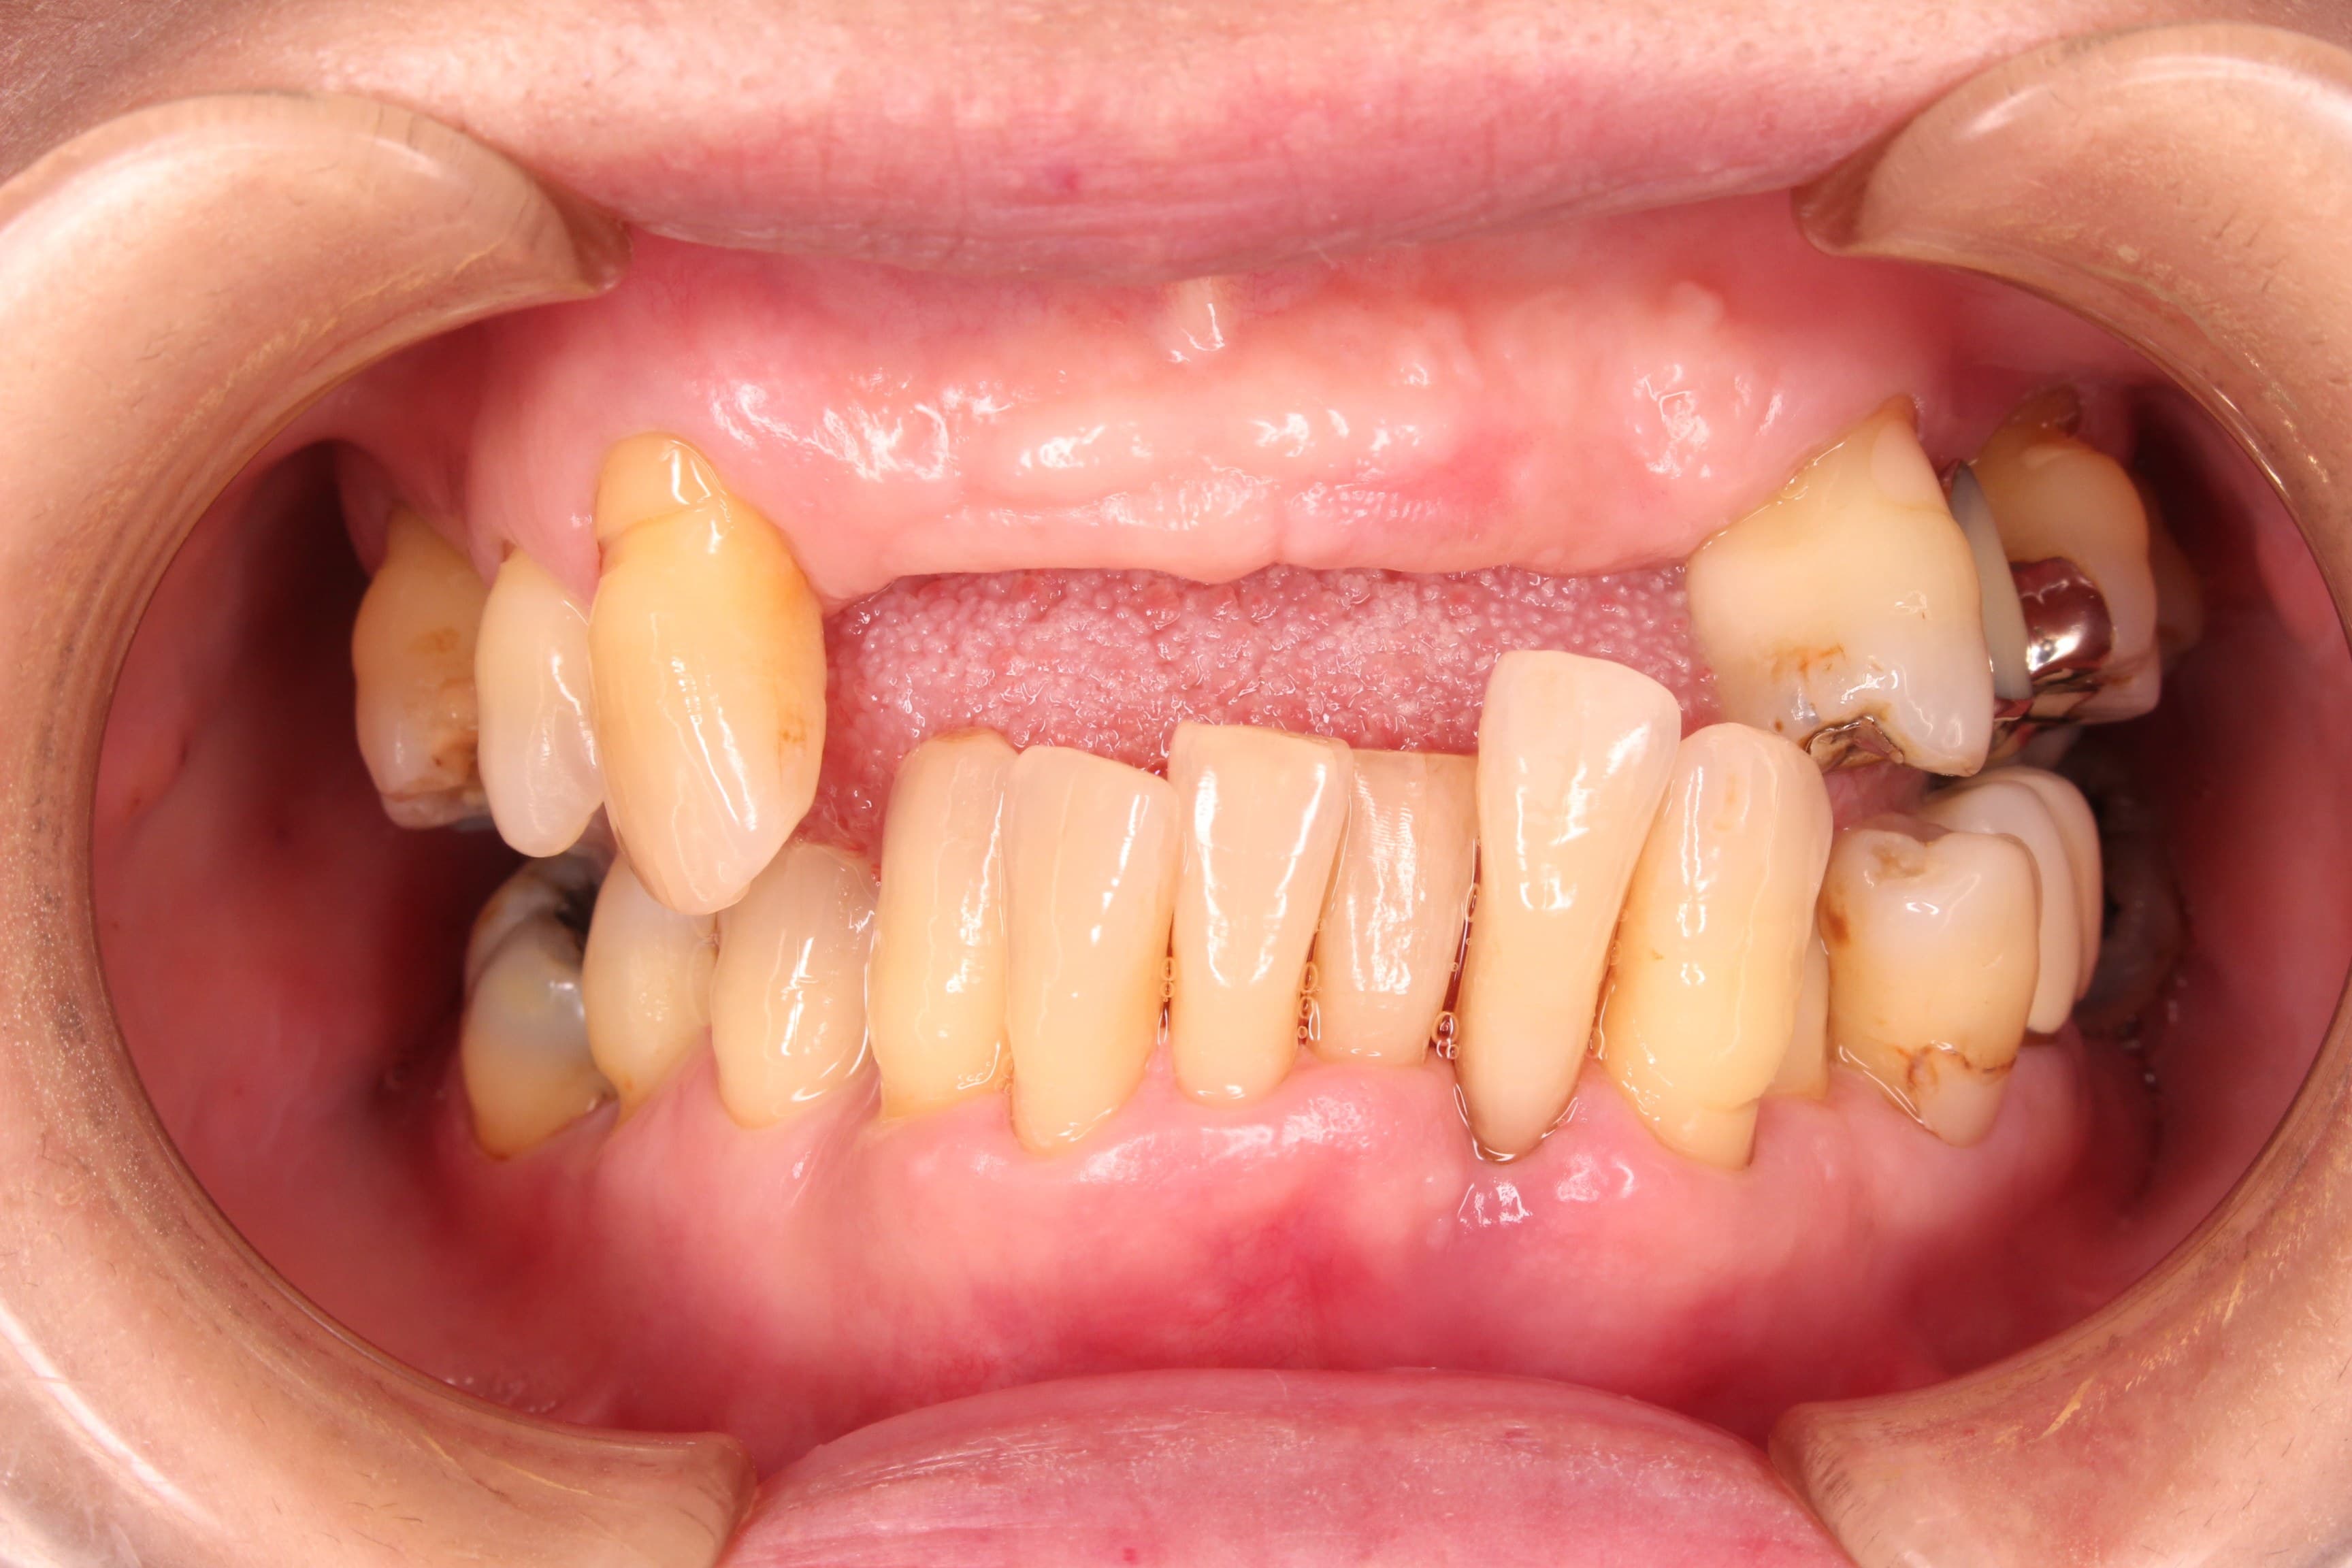

今回ご紹介する歯周専門治療のケースは、60代女性の方です。

最近になって、前歯がグラグラしてきて抜け落ちそうだという事で来院されました。

初診は2009年なのですが、約8年ぶりの来院となりました。

術前

残念ですが、失った骨を20代の頃の様に復活させることはできません。

ただ、歯槽骨(歯を支える骨)が無い歯を残すリスクをご理解いただいた上で、ギリギリまで残しておきたいというご希望に沿うよう、歯周専門治療を行いました。